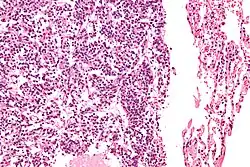

| Micrograph of a typical pulmonary carcinoid tumour. | |

The definitive diagnosis is rendered by a microscopic examination, after excision. Typical carcinoids have cells with stippled chromatin and a moderate quantity of cytoplasm. They typically have few mitoses and lack necrosis. By definition, they are greater than 4 mm in largest dimension; smaller lesions are referred to as pulmonary carcinoid tumourlets.

Very high magnification -

With prominent rosettes